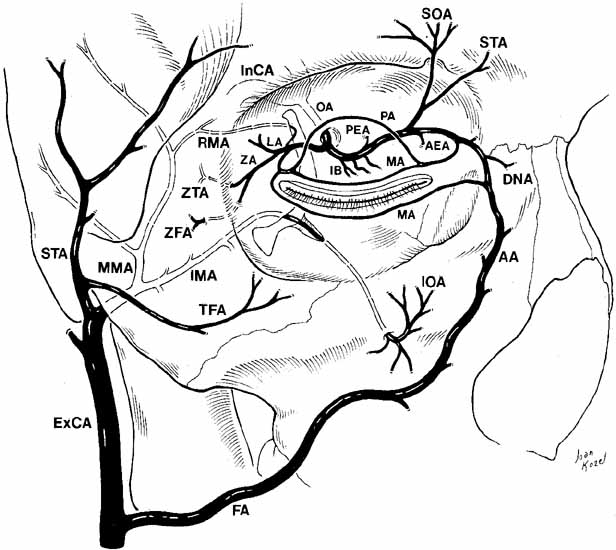

small contributions from the internal maxillary artery (Fig. 22). The internal and external carotid systems have several areas of

anastomoses for collateral circulation.  Fig. 22 Oblique view of the relationship of the internal and external carotid arterial

systems to the orbit. (ExCA, external carotid artery; FA, facial artery; AA, angular artery; IMA, internal maxillary artery; MMA, middle meningeal artery; TFA, transverse facial artery; STA, superficial temporal artery; InCA, internal carotid artery; OA, ophthalmic artery; LA, lacrimal artery; IB, intraconal branches; PEA, posterior ethmoidal artery; AEA, anterior ethmoidal artery; SOA, supraorbital artery; STA, supratrochlear artery; PA, peripheral arcade; MA, marginal arcade; ZA, zygomatic artery; ZTA, zygomaticotemporal artery; ZFA, zygomaticofacial artery; IOA, infraorbital artery; DNA, dorsal nasal artery; RMA, recurrent middle meningeal artery) Fig. 22 Oblique view of the relationship of the internal and external carotid arterial

systems to the orbit. (ExCA, external carotid artery; FA, facial artery; AA, angular artery; IMA, internal maxillary artery; MMA, middle meningeal artery; TFA, transverse facial artery; STA, superficial temporal artery; InCA, internal carotid artery; OA, ophthalmic artery; LA, lacrimal artery; IB, intraconal branches; PEA, posterior ethmoidal artery; AEA, anterior ethmoidal artery; SOA, supraorbital artery; STA, supratrochlear artery; PA, peripheral arcade; MA, marginal arcade; ZA, zygomatic artery; ZTA, zygomaticotemporal artery; ZFA, zygomaticofacial artery; IOA, infraorbital artery; DNA, dorsal nasal artery; RMA, recurrent middle meningeal artery)

|